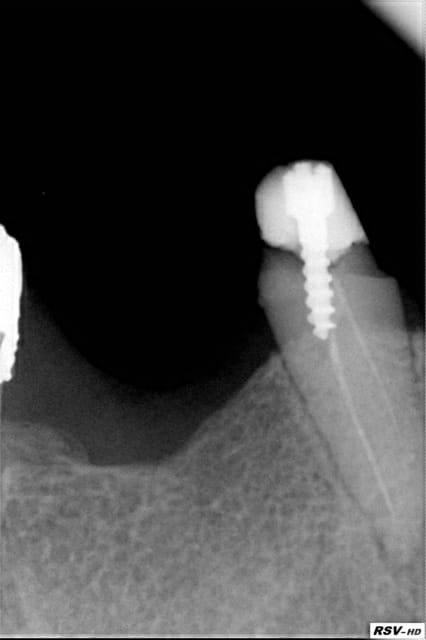

Si elle refuse l'extraction, tu peux la prévenir du risque infectieux, je trouve que le ligament est deja élargie sur ta radio et qu'elle est à surveiller et refaire son appareil.

Après, il faut voir si sur un patient lambda (et en dehors du retraitement) tu aurais décidé de garder la dent. Y a t'il une mobilité ? Joue-t'elle un rôle stratégique dans la stabilisation de la future prothèse ? Est-ce que la coiffe peut être réalisée dans de bonnes conditions ? Je n'opterais pas forcément pour l'extraction immédiate, à condition encore qu'il n'y ait pas de lésion, ce qui est difficile à juger sur ta radio vu que l'apex n'apparaît pas en entier...

Cela dépend également de l'ancienneté du traitement, de l'étanchéité de ce qui obturait la dent jusqu'ici, d'une éventuelle symptomatologie. Après tout, des dents avec un traitement très moyen qui ne présentent aucun problème particulier on en voit assez régulièrement... ;-)